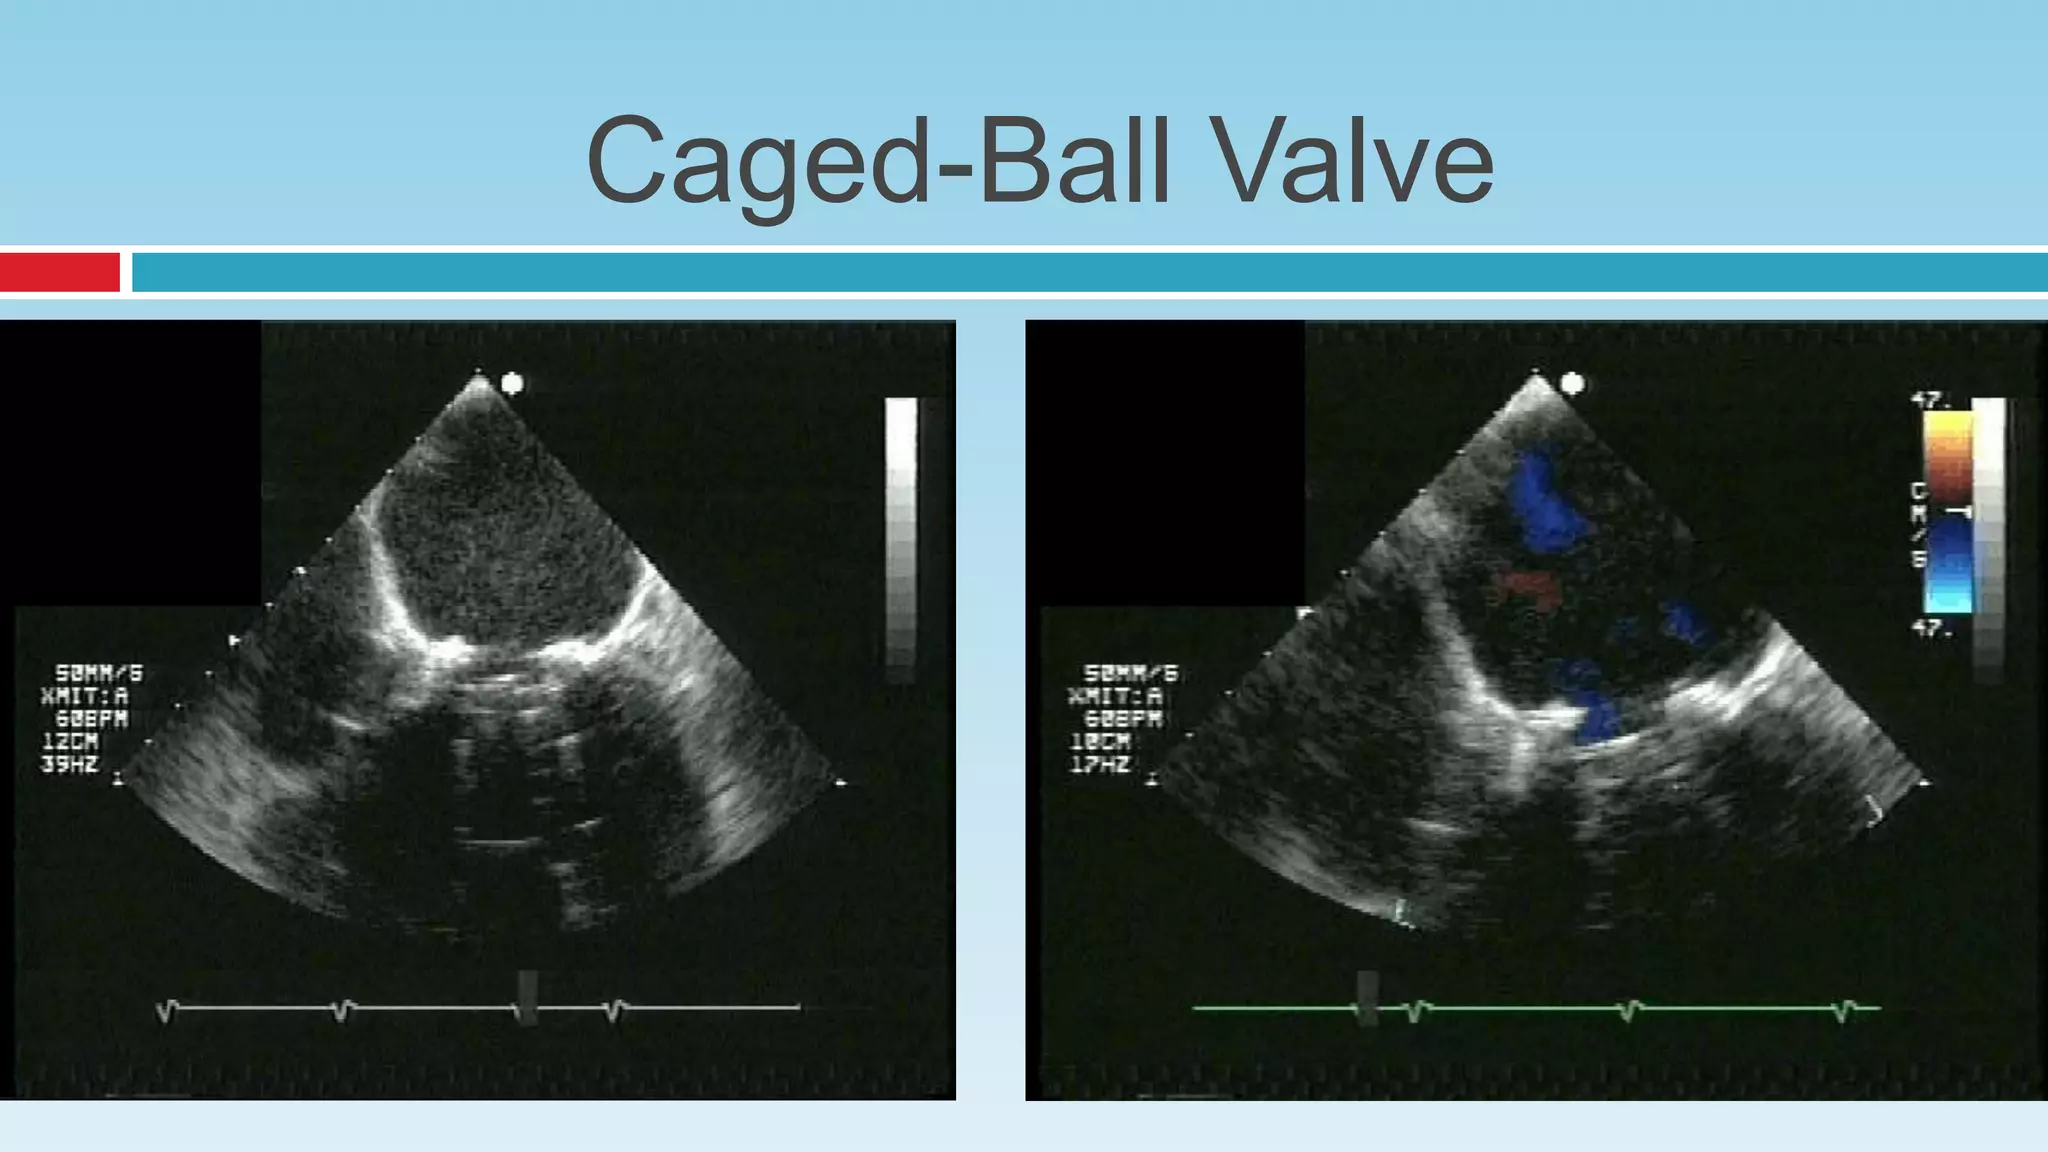

Caged-Ball Valve

 Regurgitation occurs at the disc margins

 The regurgitant jets converge toward the center of the valve